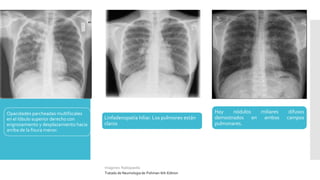

la localizacion apical de la tuberculosis pulmonar

Hallazgos radiograficos

Un infiltrado parcheado o nodular en las

Opacidades parcheadas multifocales

en el lóbulo superior derecho con

engrosamiento y desplazamiento hacia

arriba de la fisura menor.

Hay nódulos miliares difusos

demostrados en ambos campos

pulmonares.

Linfadenopatía hiliar. Los pulmones están

claros

Imagenes: Radiopaedia